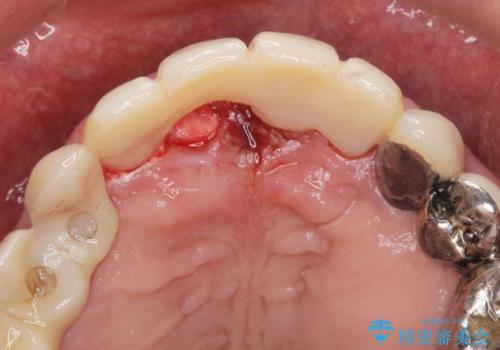

右上の前歯の抜歯を行い、ブリッジの仮歯を入れ、動揺が無くなるのを確認した後、ジルコニアクラウンブリッジを入れました。

抜歯をしてからすぐに最終的な被せ物を入れるのではなく抜歯窩がしっかり治るのを待ってから最終的な被せ物を入れていきます。

その期間は仮歯で過ごしてもらいます。